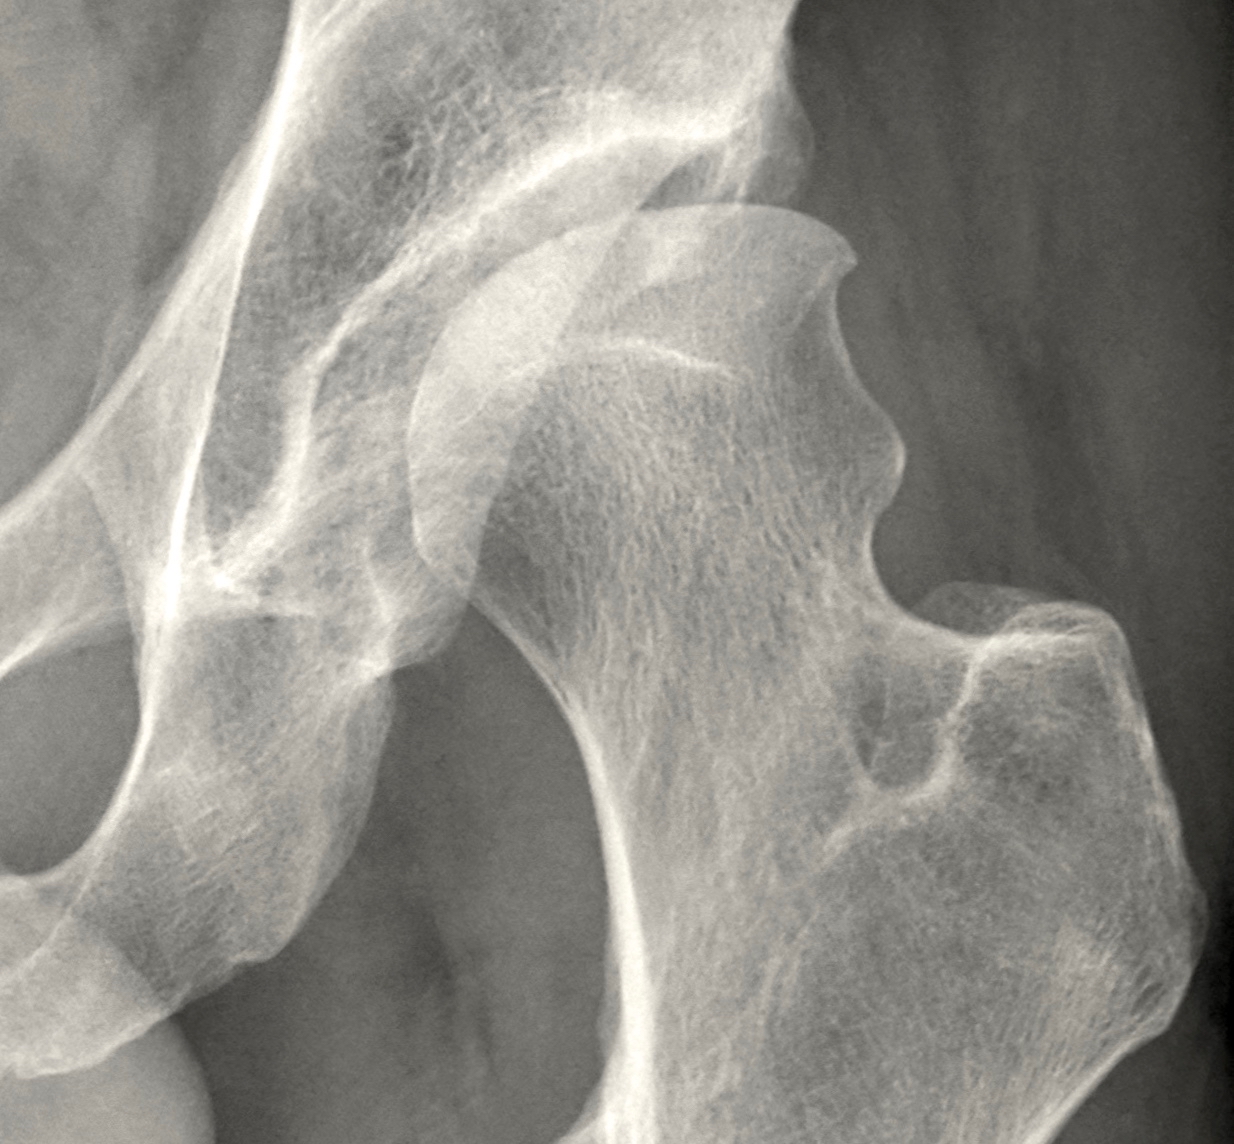

However for some, knees or hips may have deteriorated past the point of no return to where surgical intervention  the only realistic option. If this surgery is inevitable there are ways to improve your experience of it and your outcomes.

We are able to have a positive influence on both recovery and future mobility. While joint surgeries have evolved radically in the last decade, the results are often fabulous. However for some this is not the case.